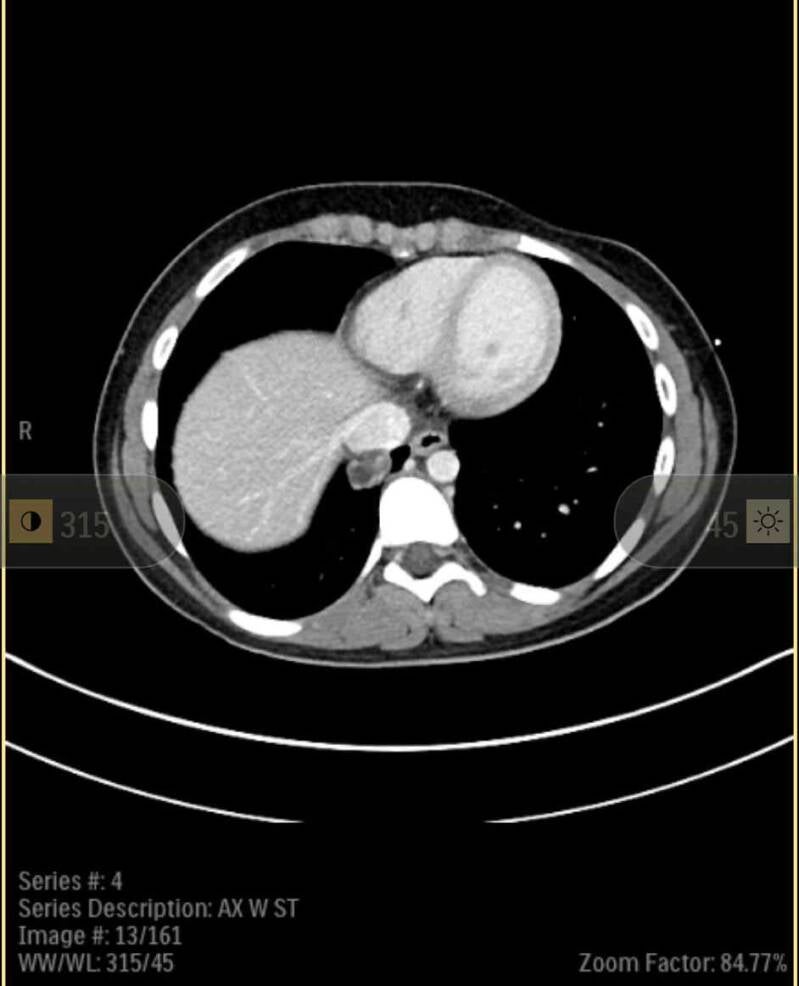

After a summer of unsuccessful medical interventions, aimed at reducing her uncontrollable nausea, Rose was hospitalized for pancreatitis. A CAT scan revealed a tumor in her lung and fluid around her pancreas. Subsequent testing revealed that the tumor was an agressive carcinoma. Rose spent an extended period of time in the hospital to help her recover from pancreatitis, and she is now on-track to begin cancer treatment.